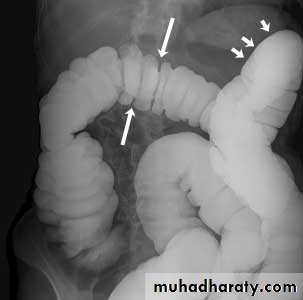

Barium small bowel follow-throughfindings of CD

Multiple mucosal ulcers aphthous ulcerslongitudinal fissures

Multiple skip lesions

when severe leads to cobblestone appearance

may lead to sinus tracts and fistulae

widely separated loops of bowel due to fibro-fatty proliferation

thickened folds due to edema

Pseudo diverticula formation: due to contraction at the site of ulcer with ballooning of the opposite site